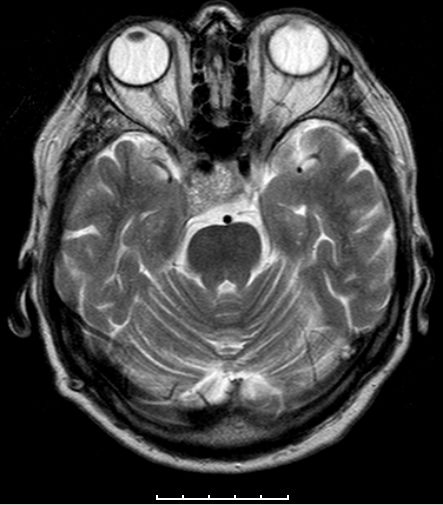

| Adenom | 78jährige Frau. Hypophysenadenom

seit 2 Jahren bekannt. Jetzt Deviation des rechten Auges und Kopfschmerzen.![]() |

![]() Das Adenom ist in die Keilbeinhöhle eingewachsen. |

![]() Infraselläre Ausbreitung mit Ummauerung der Arteria carotis interna rechts. | ||||||||||||||||||||||||||